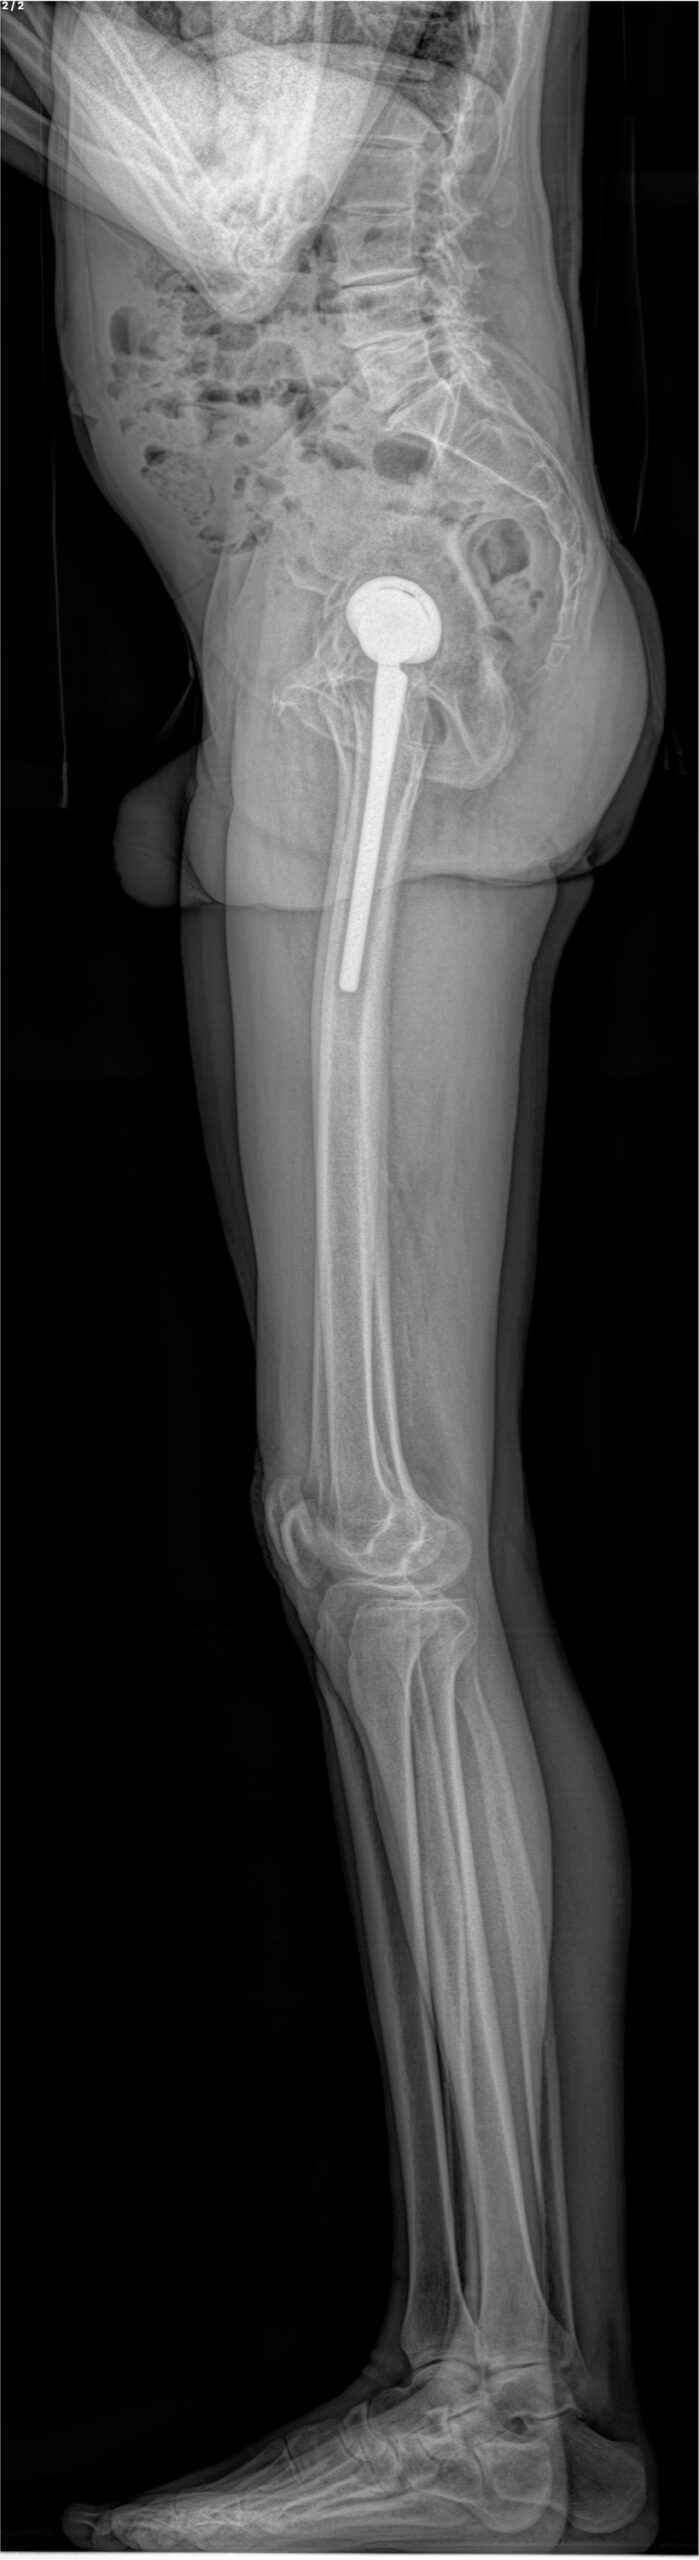

Ce système permet la réalisation de radiographies du corps entier en position debout, en une seule acquisition, sans assemblage d’images et sans distorsion verticale. Des clichés numériques de face et de profil, de tout ou partie du corps, sont obtenus simultanément avec une qualité d’image exceptionnelle et sans aucun agrandissement, garantissant une fiabilité parfaite des mesures.

À la manière d’une photocopieuse, un très fin faisceau de rayons X balaye le corps du patient de la tête aux pieds, réalisant une image de face et une de profil en quelques secondes et de manière simultanée. L’extrême sensibilité des détecteurs développés par Georges Charpak permet cette acquisition corps entier avec une dose de radiation 9 fois inférieure à celle des méthodes radiologiques classiques et jusqu’à 100 fois inférieure à celle d’un scanner.